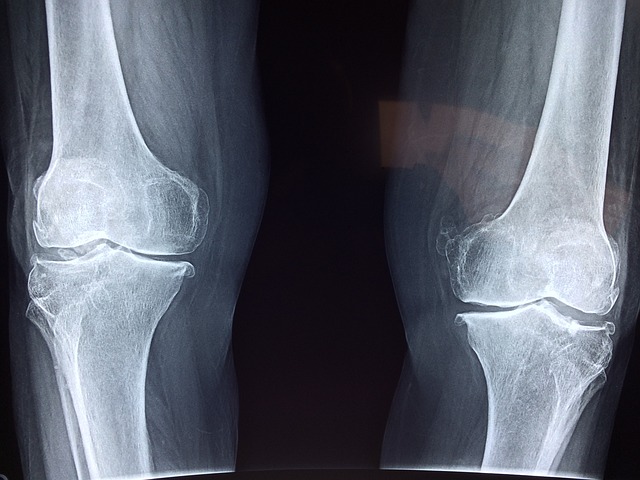

무릎 통증원인 - 퇴행성 관절염 퇴행성 관절염은 나이가 들면서 발생하는 관절의 퇴행성 변화로 인해 무릎 통증을 유발합니다. 연골이 닳아 없어지면서 뼈와 뼈가 서로 마찰되어 통증과 염증을 일으킵니다.

- 반월상 연골 파열 반월상 연골은 무릎 관절 내에서 충격을 흡수하는 역할을 합니다. 스포츠 활동이나 갑작스러운 움직임으로 인해 이 연골이 찢어질 경우, 심한 통증과 부기를 초래할 수 있습니다.

- 십자인대 손상 십자인대는 무릎의 안정성을 유지하는 데 중요한 역할을 합니다. 축구, 농구 등 격렬한 운동 중에 십자인대가 손상되면 무릎 통증과 함께 불안정성이 발생합니다.

- 슬개골 연골연화증 슬개골 연골연화증은 슬개골 하부의 연골이 부드러워지면서 통증을 유발하는 상태입니다. 주로 젊은 성인이나 운동 선수에게서 많이 나타나며, 계단을 오르내리거나 쪼그려 앉을 때 통증이 심해집니다.

- 건염 건염은 무릎 주위의 힘줄에 염증이 생기는 상태로, 반복적인 동작이나 과도한 사용이 원인입니다. 건염은 주로 달리기, 점프 등 반복적인 운동을 하는 사람들에게 많이 발생합니다.

- 무릎 외상 넘어지거나 부딪히는 등의 외상으로 인해 무릎에 직접적인 손상이 발생할 수 있습니다. 이는 골절, 타박상, 인대 손상 등으로 이어져 통증을 초래합니다.

- 류마티스 관절염 류마티스 관절염은 자가면역 질환으로, 면역 체계가 자기 몸을 공격하여 관절에 염증을 일으키는 상태입니다. 이는 무릎을 포함한 여러 관절에 통증과 변형을 일으킵니다.